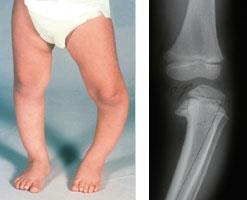

Que tiene las piernas arqueadas. La condición hace que las rodillas de una persona queden muy separadas mientras está de pie con los pies y los tobillos juntos con la aparición de la forma de la proa de un arquero. Fruto conocido como semáforo por sus 3 colores. Piernas arqueadas Bowed Legs Las piernas arqueadas en un niño pequeño son muy comunes.

Las piernas arqueadas también llamadas Genu Varo son una deformidad física que lleva a las piernas a inclinarse hacia el exterior con relación al muslo. El arco que hasta ahora es normal debería desaparecer cuando tu bebé tenga aproximadamente los 3 años de edad. Las patas de arco a veces pueden ser un signo de una enfermedad subyacente como la enfermedad de Blount o el raquitismo y pueden provocar artritis en las.

No hay que buscar una explicación. Las piernas arqueadas son una condición en la cual las piernas de una persona aparecen arqueadas lo que significa que sus rodillas se mantienen separadas incluso cuando sus tobillos están juntos. En cambio a medida que crecen se corrige y ya no deberían tenerlas arqueadas durante la niñez ni mucho menos en la adolescencia.

Efectivamente las piernas arqueadas en un niño o niña pequeño son muy comunes. Las piernas en forma de paréntesis o piernas arqueadas se denominan en términos médicos genu varum lo que quiere decir que las rodillas están separadas entre sí los tobillos juntos y las tibias curvas.